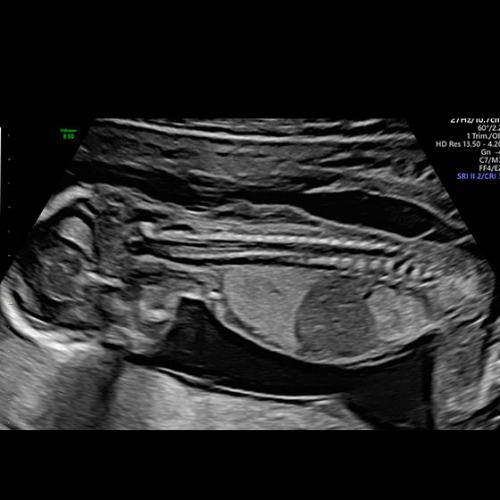

The first trimester — the first 13 weeks of pregnancy — is perhaps the most transformative period in...

Got you — here’s a clean, authoritative yet super-readable pillar page on First Trimester Screening,...

Fetal Well-being Scan Red Flags: What Parents Need to Know in Kolkata